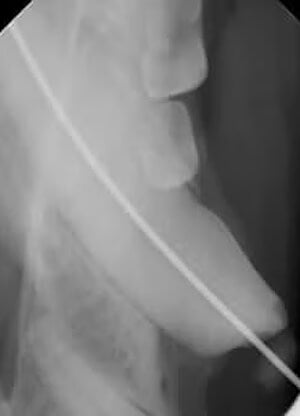

Any chipped or discolored tooth may have a root canal (endodontic) problem. They are usually diagnosed on the physical exam after the heavy tartar is removed and when an abscess is seen at the tip or apex of the tooth on a radiograph.